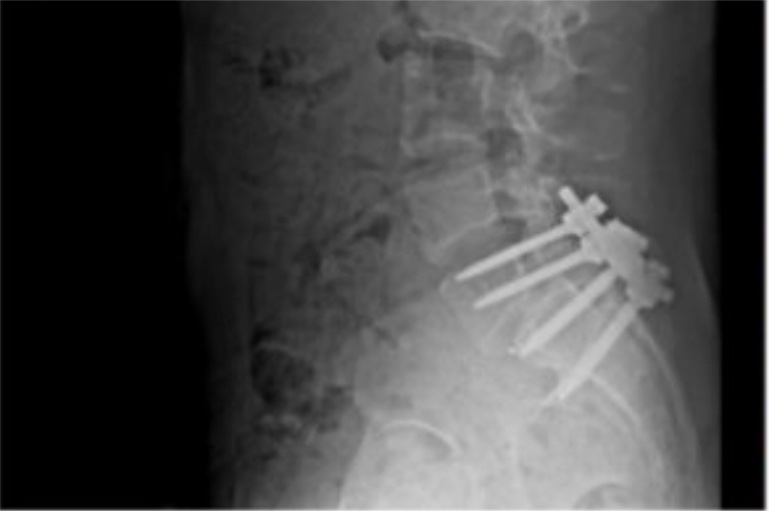

Holy mackerel, check the heavy grip on his surgically repaired neck.

I stand corrected. Surgery was L-5, lower back, not neck.